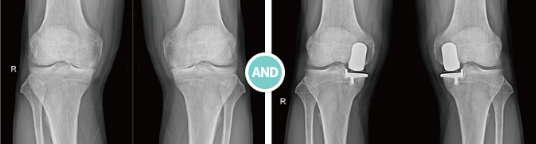

무릎 인공관절 반치환술(UKR)

인공관절 반치환술을 ‘부분 치환술’이라고도 합니다. 본인의 관절을 최대한 보존하기 위한 방안으로 관절 손상이

부분적일 경우 시행하게 됩니다. 관절면의 손상이 고르게 진행되는 것이 아니라 내측 연골부터 손상이 시작되기 때문에

이러한 대상자들에게 국한되어 적용됩니다.

좌식문화를 가진 동양인들은 양반다리나 무릎을 접어 앉는 자세로 인해 내측 관절에 스트레스가 가중되어

이 같은 경우가 흔히 발생합니다. 대부분의 관절염 환자들은 내측 연골부터 천천히 마모가 진행되는데,

보존적 치료에도 불구하고 관절염의 진행이 계속되면 인공관절 반치환술을 통해 통증 완화 및 관절기능을 회복시킵니다.

수술 후 재활이 매우 빨라 일상생활로의 복귀에 용이합니다.